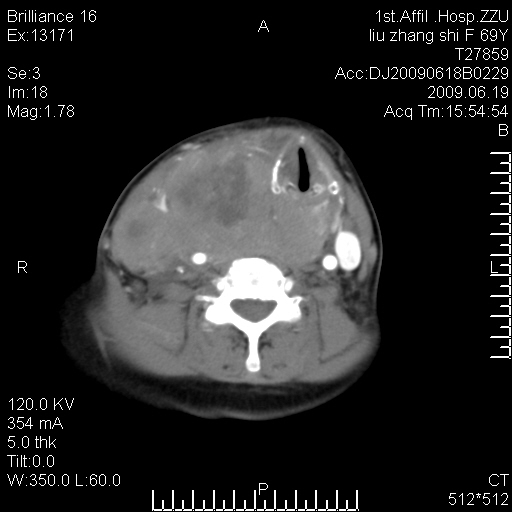

标题: CT26782:女,69岁,颈部占位,3天后公布病理结果。

【病理证实系列】女,69岁,颈部占位,有病理结果,3天后公布。(由于病例时间较久,临床资料不全,请网友见谅)本系列将有几百种常见、少见及罕见病例,均经病理证实。病例资料来自郑州大学第一附属医院。与网友共享,本人有空就发。

甲状腺癌并颈部淋巴结转移。感谢楼主的良苦用心,谢谢。

甲状腺癌并颈部淋巴结转移。

需与鼻咽癌鉴别!

支持甲状腺癌广泛侵及周围结构并颈部淋巴结转移。

鉴别:淋巴瘤、恶性神经源性病变、恶性纤维组织细胞瘤。

病理结果:颈部非霍奇金淋巴瘤。